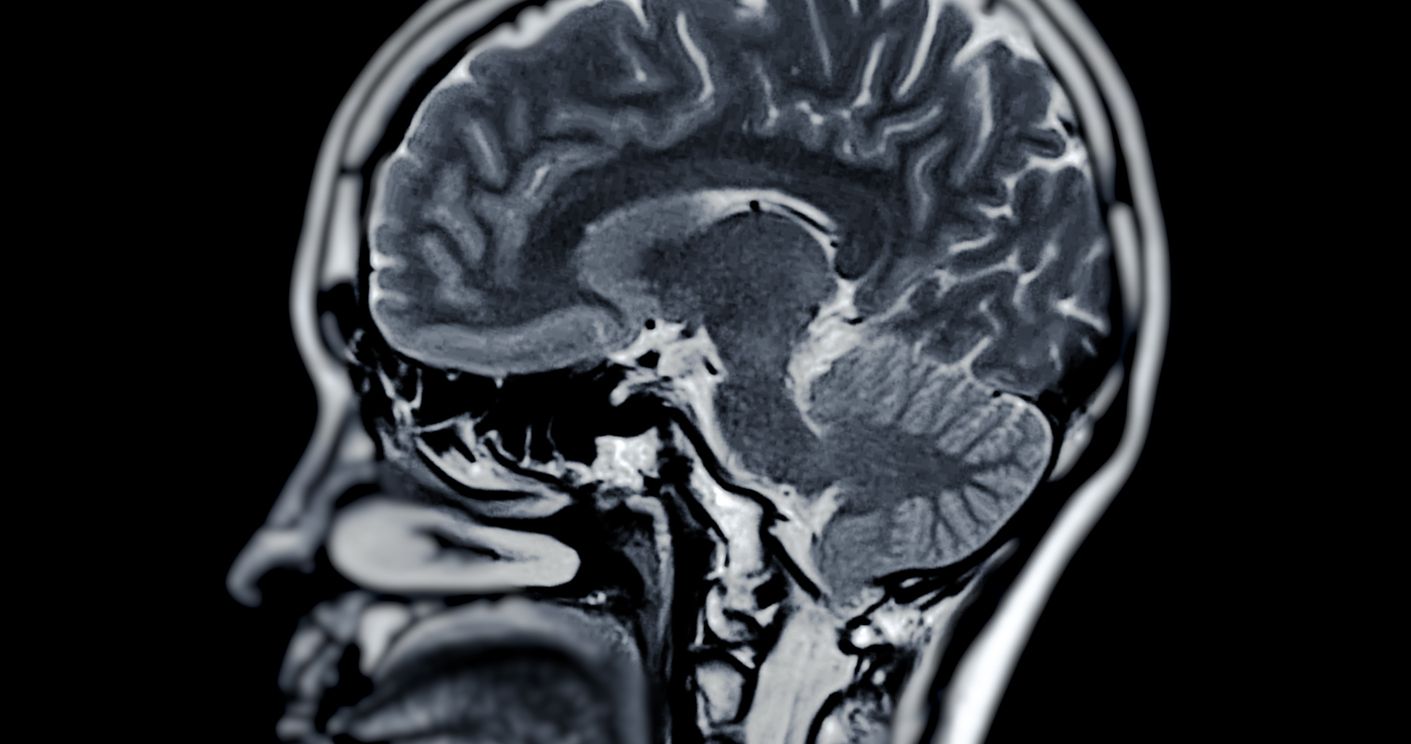

Ein Schlaganfall (Apoplex) tritt auf, wenn die Blutzufuhr zum Gehirn unterbrochen wird und die Gehirnzellen absterben. In 80 % der Fälle wird er durch den Verschluss einer Arterie im Gehirn ausgelöst. Die Schäden können zu langfristigen körperlichen und/oder geistigen Behinderungen führen und im schlimmsten Fall tödlich sein.